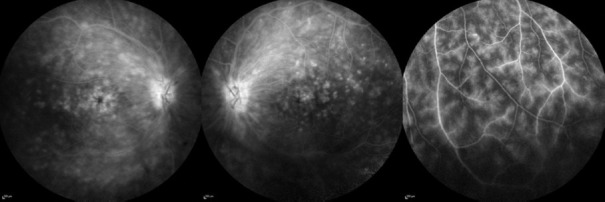

Behçet's uveitis (BU) is a significant form of major organ involvement in Behçet syndrome and is associated with considerable morbidity. Ocular examination is crucial for diagnosing BS and detecting vitreous cells, even in asymptomatic patients. The primary goals in managing BU are to rapidly suppress ocular inflammation and prevent relapses. Initial treatment for posterior segment involvement in BU typically involves immunosuppressive agents combined with glucocorticoids. Biologic agents are increasingly used in BU management, including as first-line treatments for patients with poor prognostic risk factors or sight-threatening uveitis. There is no established consensus on when to discontinue or taper immunosuppressive therapy. Once remission is achieved, the absence of retinal vasculitis should be confirmed with fluorescein angiography, which should be utilized throughout the process of tapering immunosuppressive therapy. In addition to monoclonal tumor necrosis factor-alpha antagonists and tocilizumab, Janus kinase inhibitors may offer the potential for managing BU in the future.

Abstract Image